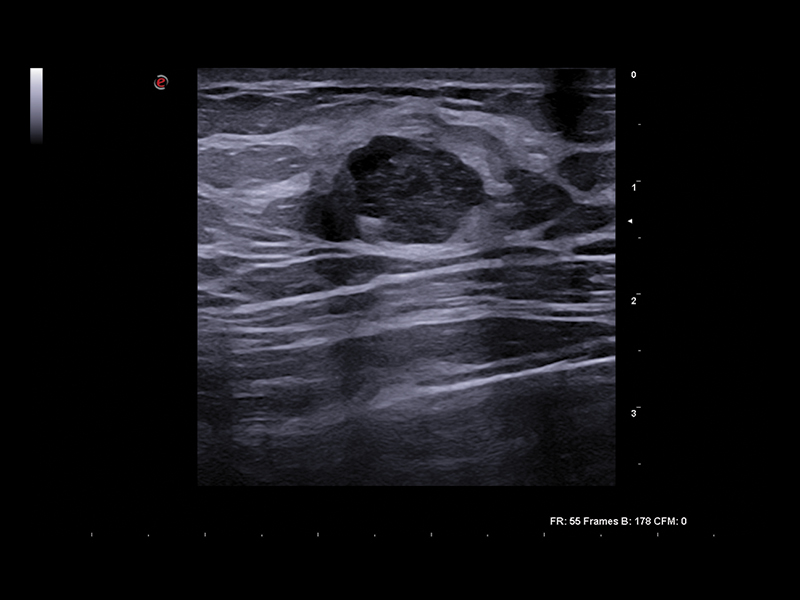

Performing breast imaging properly is the key to providing the best possible treatment. The Esaote-developed XCrystal technology dramatically increases sensitivity and penetration, to provide an unparalleled level of detail imaging, from the ultra-near-field to deeper areas. Applied to these high-density elements according to a multi-layer matrix structure array, the new Esaote LMX 4-20 transducer technology enables unparalleled sharp and clear imaging to achieve excellence in breast ultrasound examinations.

Clinical Images

Breast clinical image